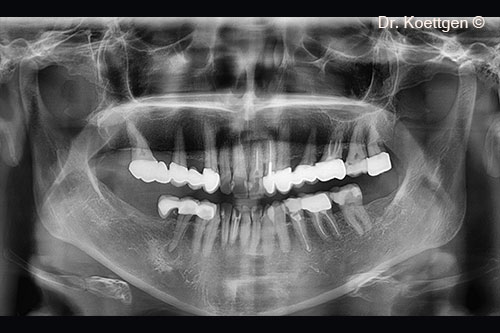

11. OPG - final